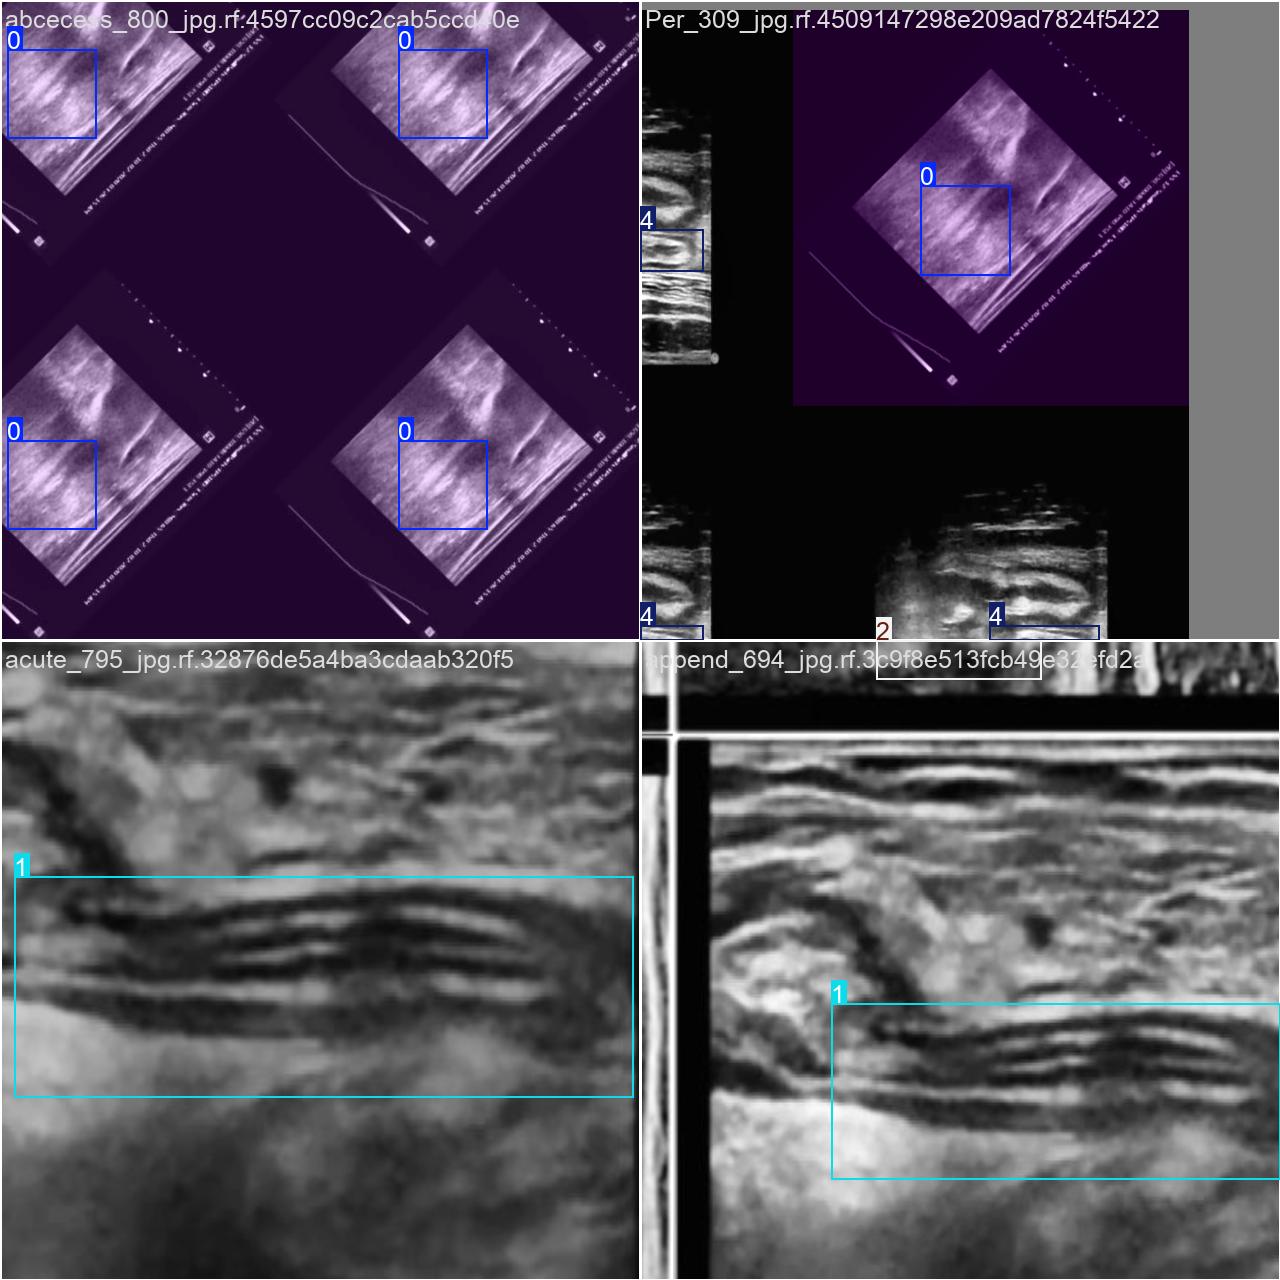

目标检测训练数据可视化

目标检测训练过程中,模型对数据的可视化结果,主要展示了多个类别目标的检测边框和类别标注情况。整体检测表现较好,但可以通过优化标注和模型训练进一步提升精度和鲁棒性。